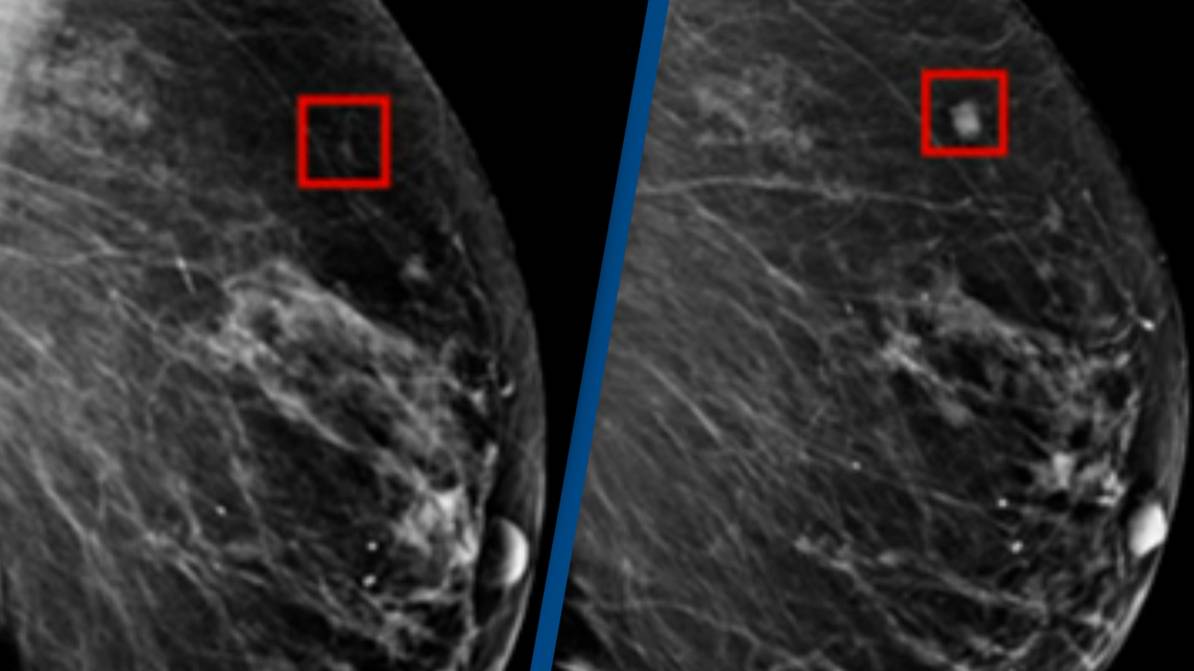

๐ฉโโ๏ธ AI Detects Breast Cancer 4 Years in Advance - Revolutionary Advancement in Early Diagnosis!